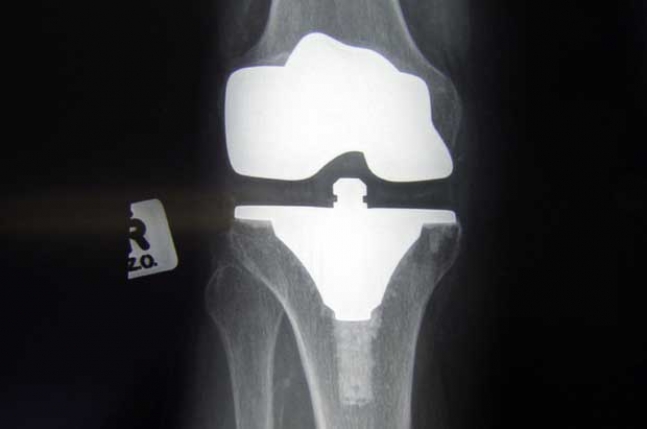

Koljena – Zašto koljena pucaju kada se spustimo u čučanj? Zato što ih spuštanjem opterećujemo s težinom koja je sedam puta veća od naše ukupne tjelesne težine što bi značilo da tkivo protestira. Najbolji način za rješavanje ovog problema kao i očuvanja koljena su vježbe i jačanje mišića koji drže koljeno.